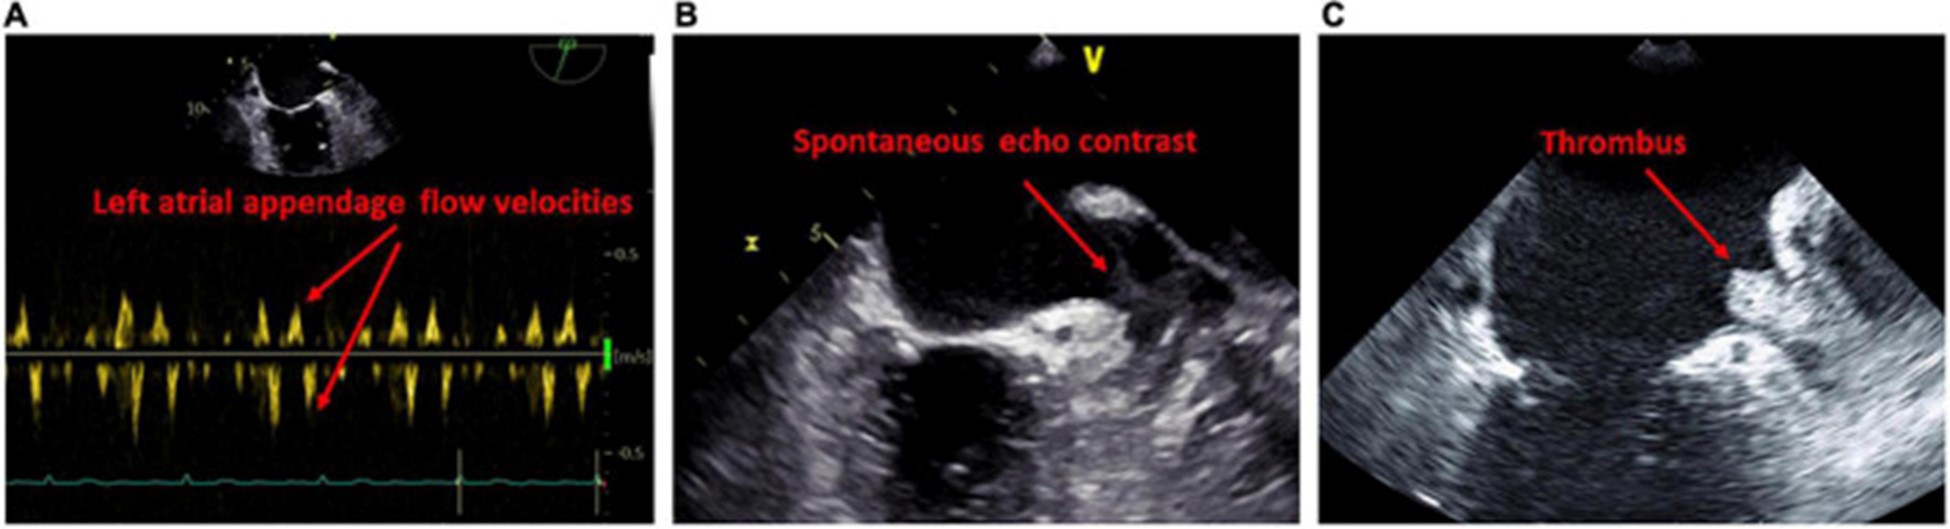

经食道超声心动图

经食道超声心动图的一个重要优势是更正确地评估左心耳。关于经食管异常与左心房心肌病相关性的证据有限,LACM 主要通过延迟增强 MRI 确定纤维化来确定。经晚期钆增强 MRI 诊断,与没有血栓的患者相比,有 LA 附肢血栓的患者有更多的 LA 纤维化 。有自发回声对比的患者的 LA 纤维化程度甚至高于没有的患者。此外,高心房纤维化患者更可能在左心耳同时出现血栓和自发回声对比(70)。众所周知,LA/LA 附件血流动力学减少和 LA 大小增加是血栓和自发回声对比发生的危险因素 (图 4)。

图 4:经食道检查提示左心房心肌病的结果。(A)左心耳口的血流减少。(B)左心耳自发回声对比的证据。(C)左心耳血栓的证据。